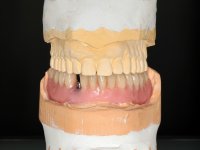

Two dental implants were planned in the CBCT scan, in the area of the inferior canines. The dental extractions were performed and, simultaneously, the alveolar crest was flattened and the implants were placed. Three issues were considered while implant placement: parallelism of the axis, same height of the implant’s neck, and same position in the coronal plan. This 3D insertion is essential to have a good retention of the overdenture in the future. Patient’s removable denture was fixed in the dental lab, to include the extracted teeth, and a soft-tissue relining was done over the healing abutments. After the osseo-integration period, a first impression was done with an open-tray and a doble-mix technique. This dental impression allowed the production of screwed wax-rims and an individual tray for a functional impression. A second impression, final, was done with an individual tray with a monophasic silicone. The occlusal wax-rims were correct in the mouth according to the full denture guidelines. Special care was taken with the occlusal vertical dimension and the support in the soft-tissues. A silicone bite registration material was used to better defined the intermaxillary relations. Teeth set-up was done in the dental lab with the selected tooth color. Due to the fact that the base was screwed to the dental implants, the teeth set-up was functionally evaluated in the mouth. Another silicone bite registration material was used to allow final occlusal adjustments. Finally, the locators were screwed and the retention nylons were selected according to the patient needs.